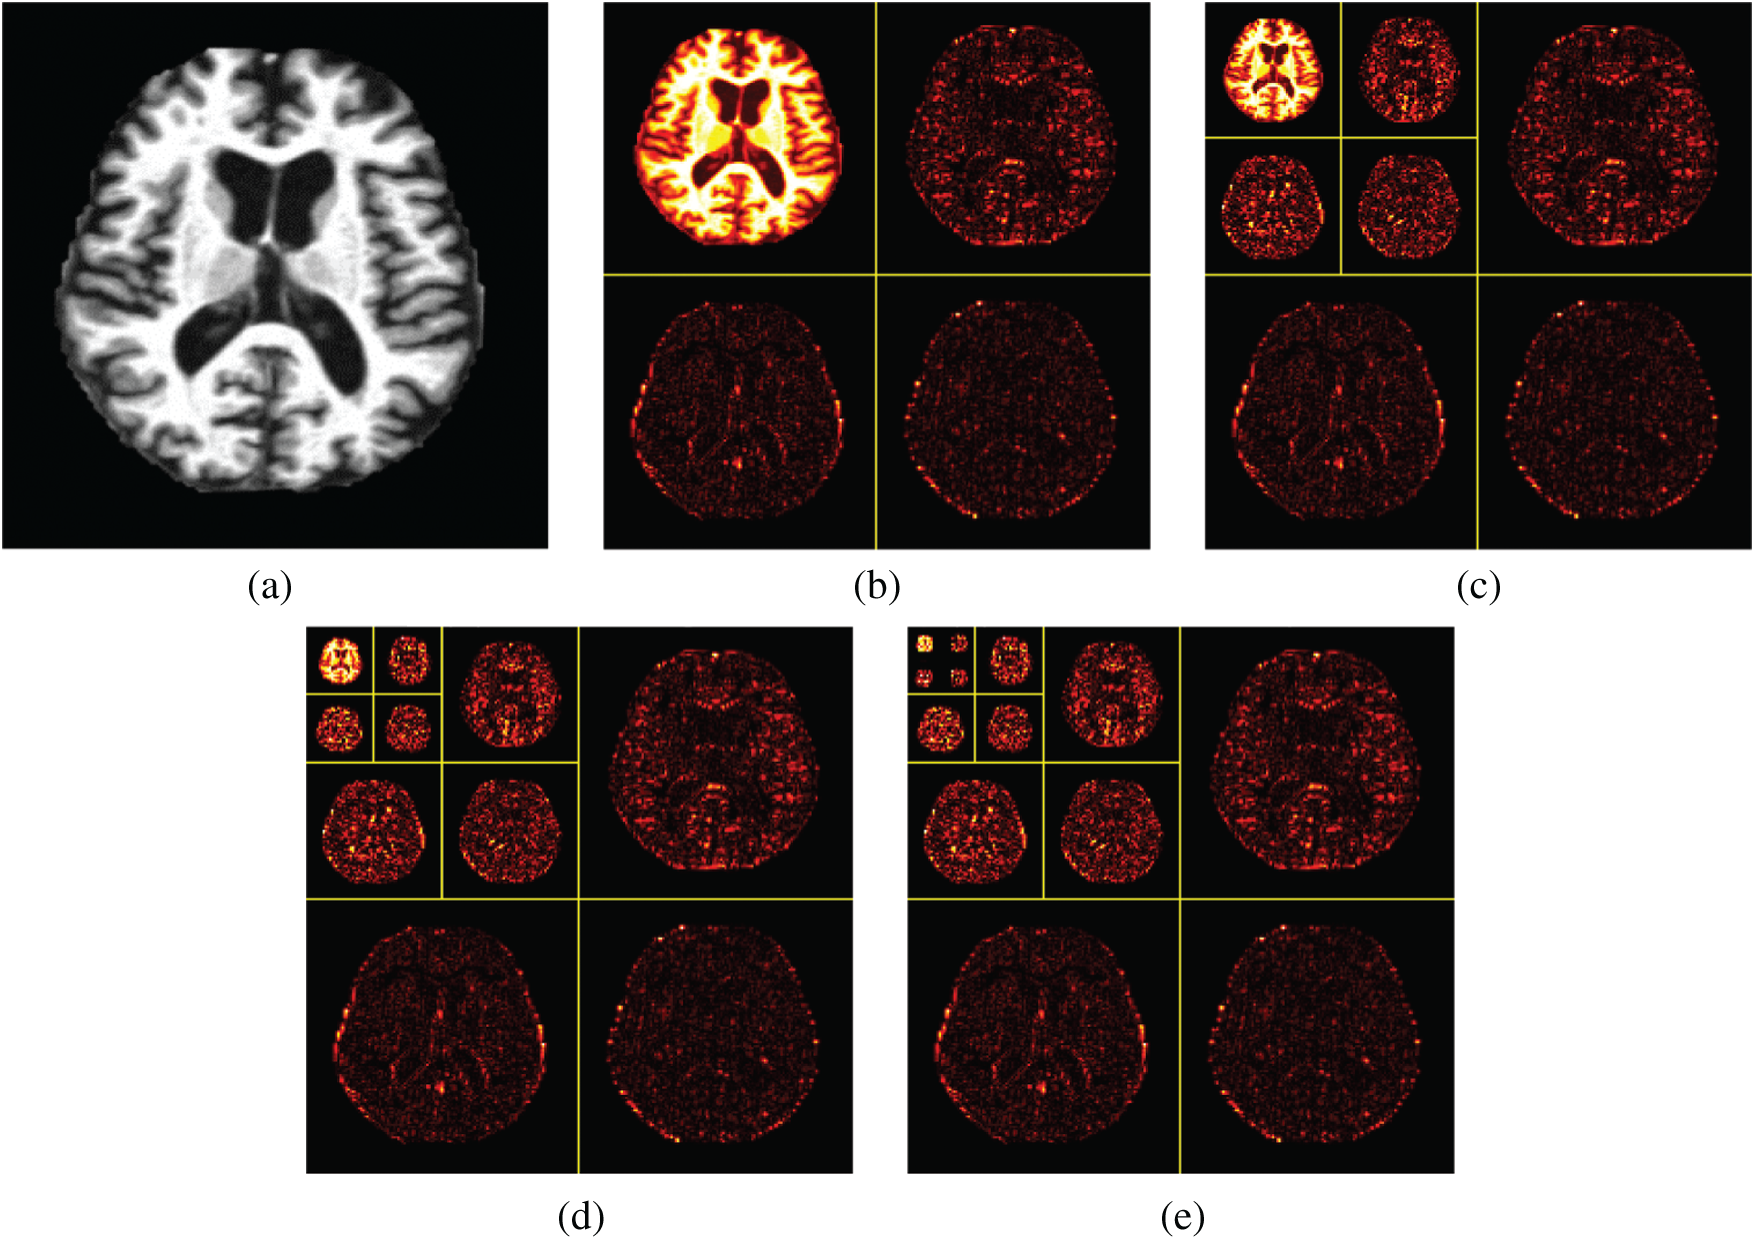

The wavelet decomposition of magnetic resonance imaging is shown in the Fig. 4, and the process is summarized as follows: Firstly, the image signal is decomposed into two parts: Low-frequency approximation and high frequency detail. Next, we will continue to divide the low frequency approximation part into the low frequency approximation and the high frequency detail part, and then decompose the low frequency approximation part to only one point in each part. The high frequency details are not decomposed each time.

Figure 4: Wavelet decompositions. (a) Raw image (b) Level 1 decomposition (c) Level 2 decomposition (d) Level 3 decomposition (e) Level 4 decomposition